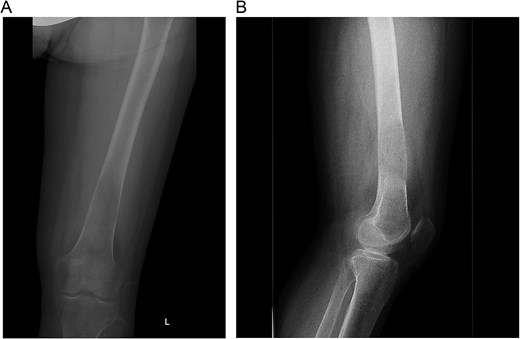

A multidisciplinary discussion involving orthopedic, maternal-fetal medicine, and head and neck teams determined the treatment plan. Further biopsy confirmed the brown tumor diagnosis, showing multinucleated giant cells, mononuclear stromal cells, bone resorption, and osteoclast clustering (Fig. 2A–C). Six days after the presentation, she was deemed suitable for parathyroidectomy. Although at high risk for pathologic fracture, she declined prophylactic fixation during pregnancy. Two days after a successful parathyroidectomy, she underwent an uncomplicated Cesarean section. As her calcium levels normalized, plans for femoral fixation were made post-childbirth. One week postpartum, the patient fell, resulting in a pathologic fracture of the left distal femur and ipsilateral iliac wing fracture (Fig. 3A and B).

(A–C). Histopathologic images from biopsy specimen at 100× and 200× magnification, showing numerous multinucleated giant cells and mononuclear stromal cells with marked resorption of bone trabeculae and clustering of osteoclasts.